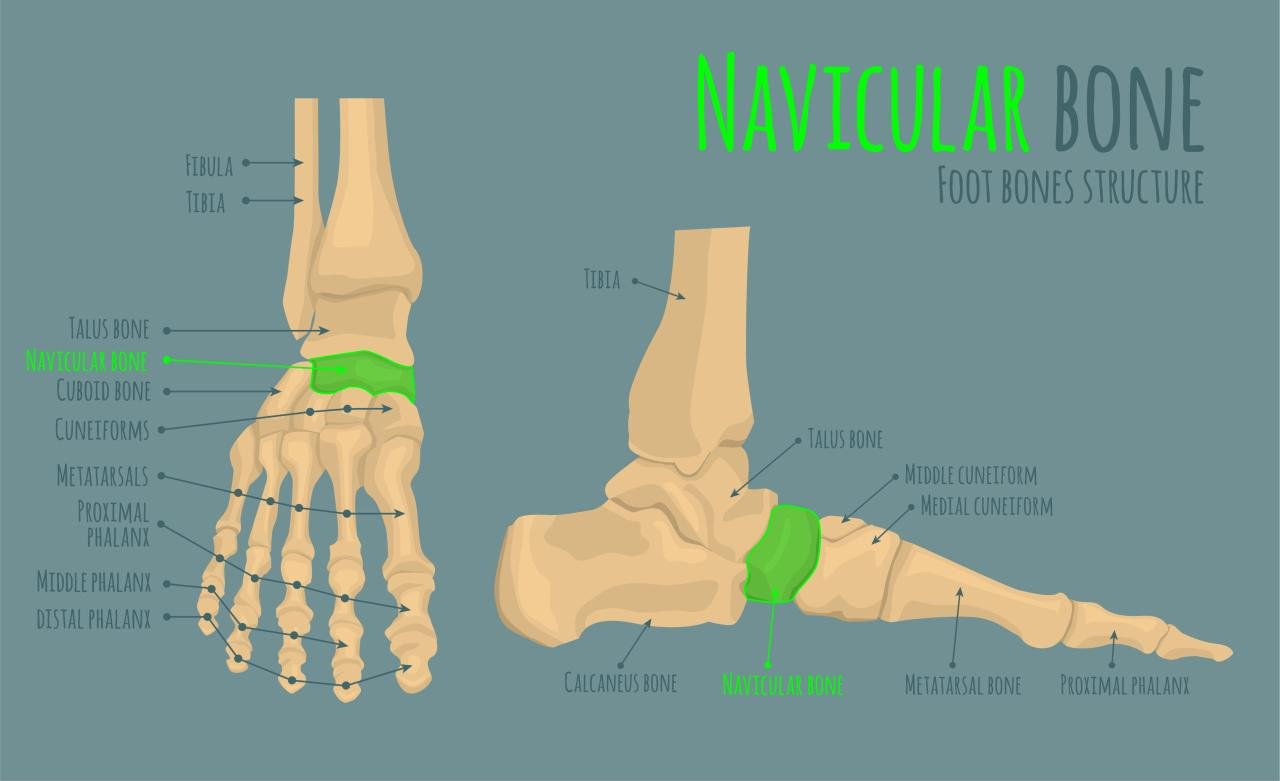

What is the accessory navicular syndrome?

Accessory navicular syndrome occurs when an extra bone, known as the accessory navicular, causes pain and discomfort in the foot, often due to overuse or misalignment.

How is the surgery performed?

The surgery typically involves the removal of the accessory navicular bone, which relieves pressure on surrounding tissues and alleviates pain.